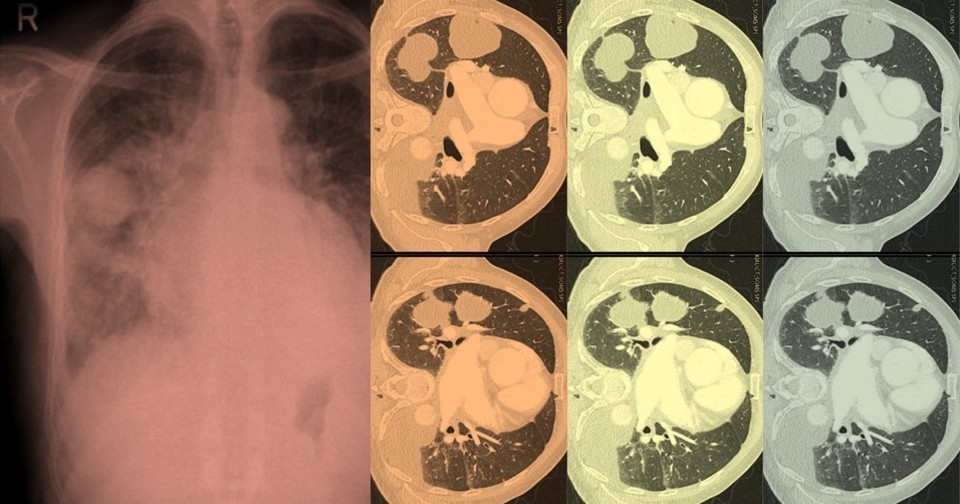

Рентгенография органов грудной клетки выявила четко выраженное двояковыпуклое затемнение размером 5 на 4 сантиметра в правом легком. Учитывая стаж курения пациента, врачи предположили, что образование в легком может быть злокачественной опухолью легкого. Компьютерная томография, однако, показала, что вдоль щелей между долями правого легкого скопилась жидкость, а в левом легком наблюдается значительный плевральный выпот. В результате пациенту поставили диагноз застойной сердечной недостаточности, которая сопровождается псевдоопухолью легкого.